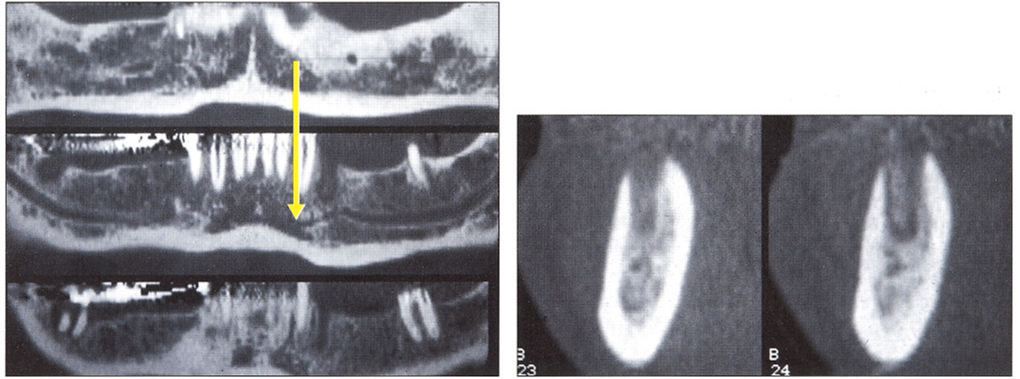

Рис. 18-4 и 18-5. На томограмме точно определяется положение нижнечелюстного канала, а также резцового канала (стрелка), который был обнаружен только благодаря этой методике.